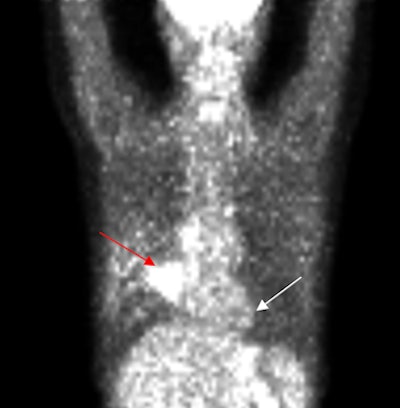

| PET scan, above, indicates the presence of a large tumor (red arrow); the corresponding ECDG-SPECT image, below, also defines the presence of the mass (red arrow). The FDG-PET image also shows benign pulmonary nodules (white arrow), which are not see on the ECDG-SPECT image, indicating they are not representative of cancer. Images courtesy of F. David Rollo, MD, PhD, and Cell>Point. |

The study found that ECDG-SPECT matched FDG-PET in image interpretation for all primary lesions. With FDG-PET, the researchers wrote, primary lesions had a "fluffy appearance and were larger than noted on pretreatment PET, consistent with chemotherapy inflammatory response. For SPECT, the primary lesions were smaller and more discrete, consistent with clinical findings of chemotherapy efficacy."